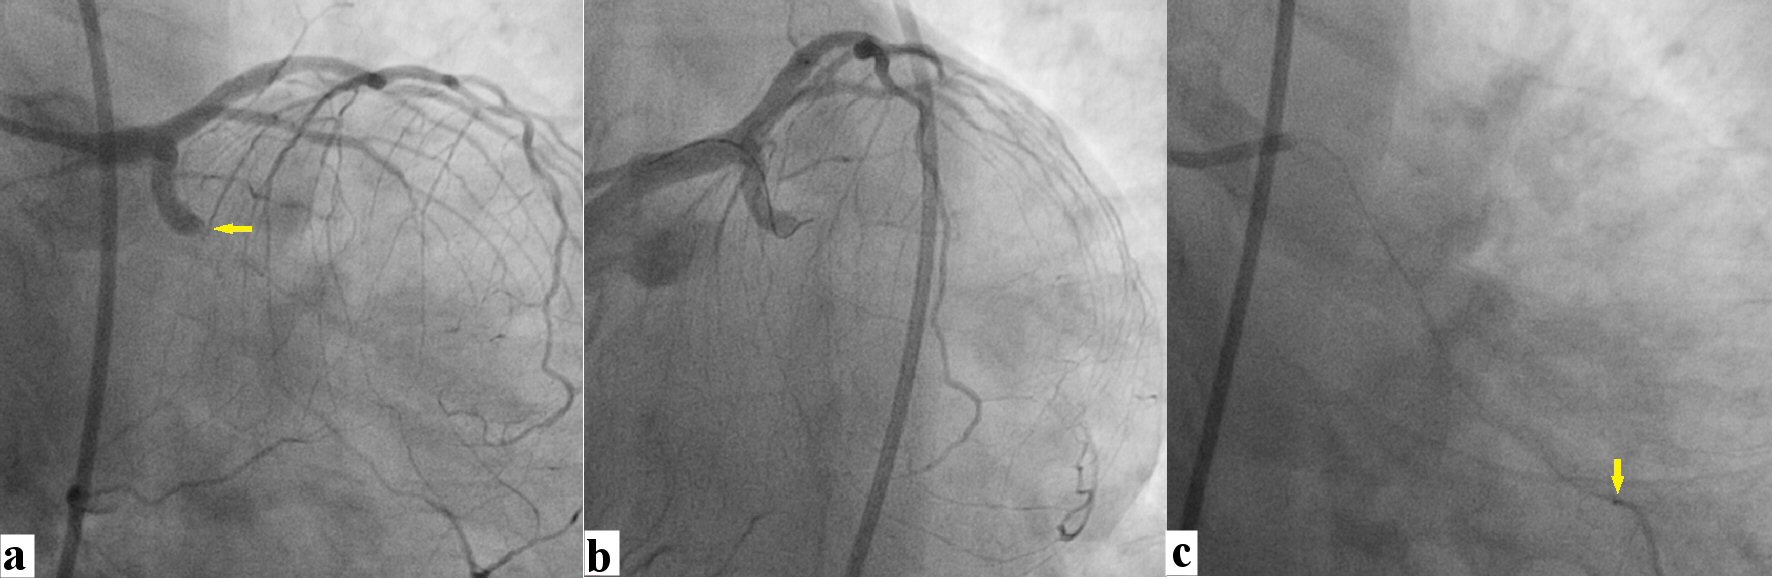

![]() Click for large image | Figure 3. (a) Distal obtuse marginal branch was wired with Sion blue wire (Asahi Inc, Japan; A). (b) It was stented with 3.5 × 38 Endeavour Resolute (Zotarolimus eluting stent, Medtronic; USA). (c) Ostial severe disease of distal circumflex branch (yellow arrow). |

![]() Click for large image | Figure 4. (a) Distal circumflex branch was rewired using Sion black wire. (b, c) After pre-dilatation of distal LCX, stent could not be negotiated into it because of tortuosity and calcification. A 3 × 10 Sprinter NC balloon (Medtronic Inc.; Japan) was used as deflection balloon which was kept little inside at proximal part of LCX (yellow arrow) and 2.75 × 12 mm Endeavour Resolute stent was successfully delivered into distal LCX (double arrow). LCX: left circumflex artery. |